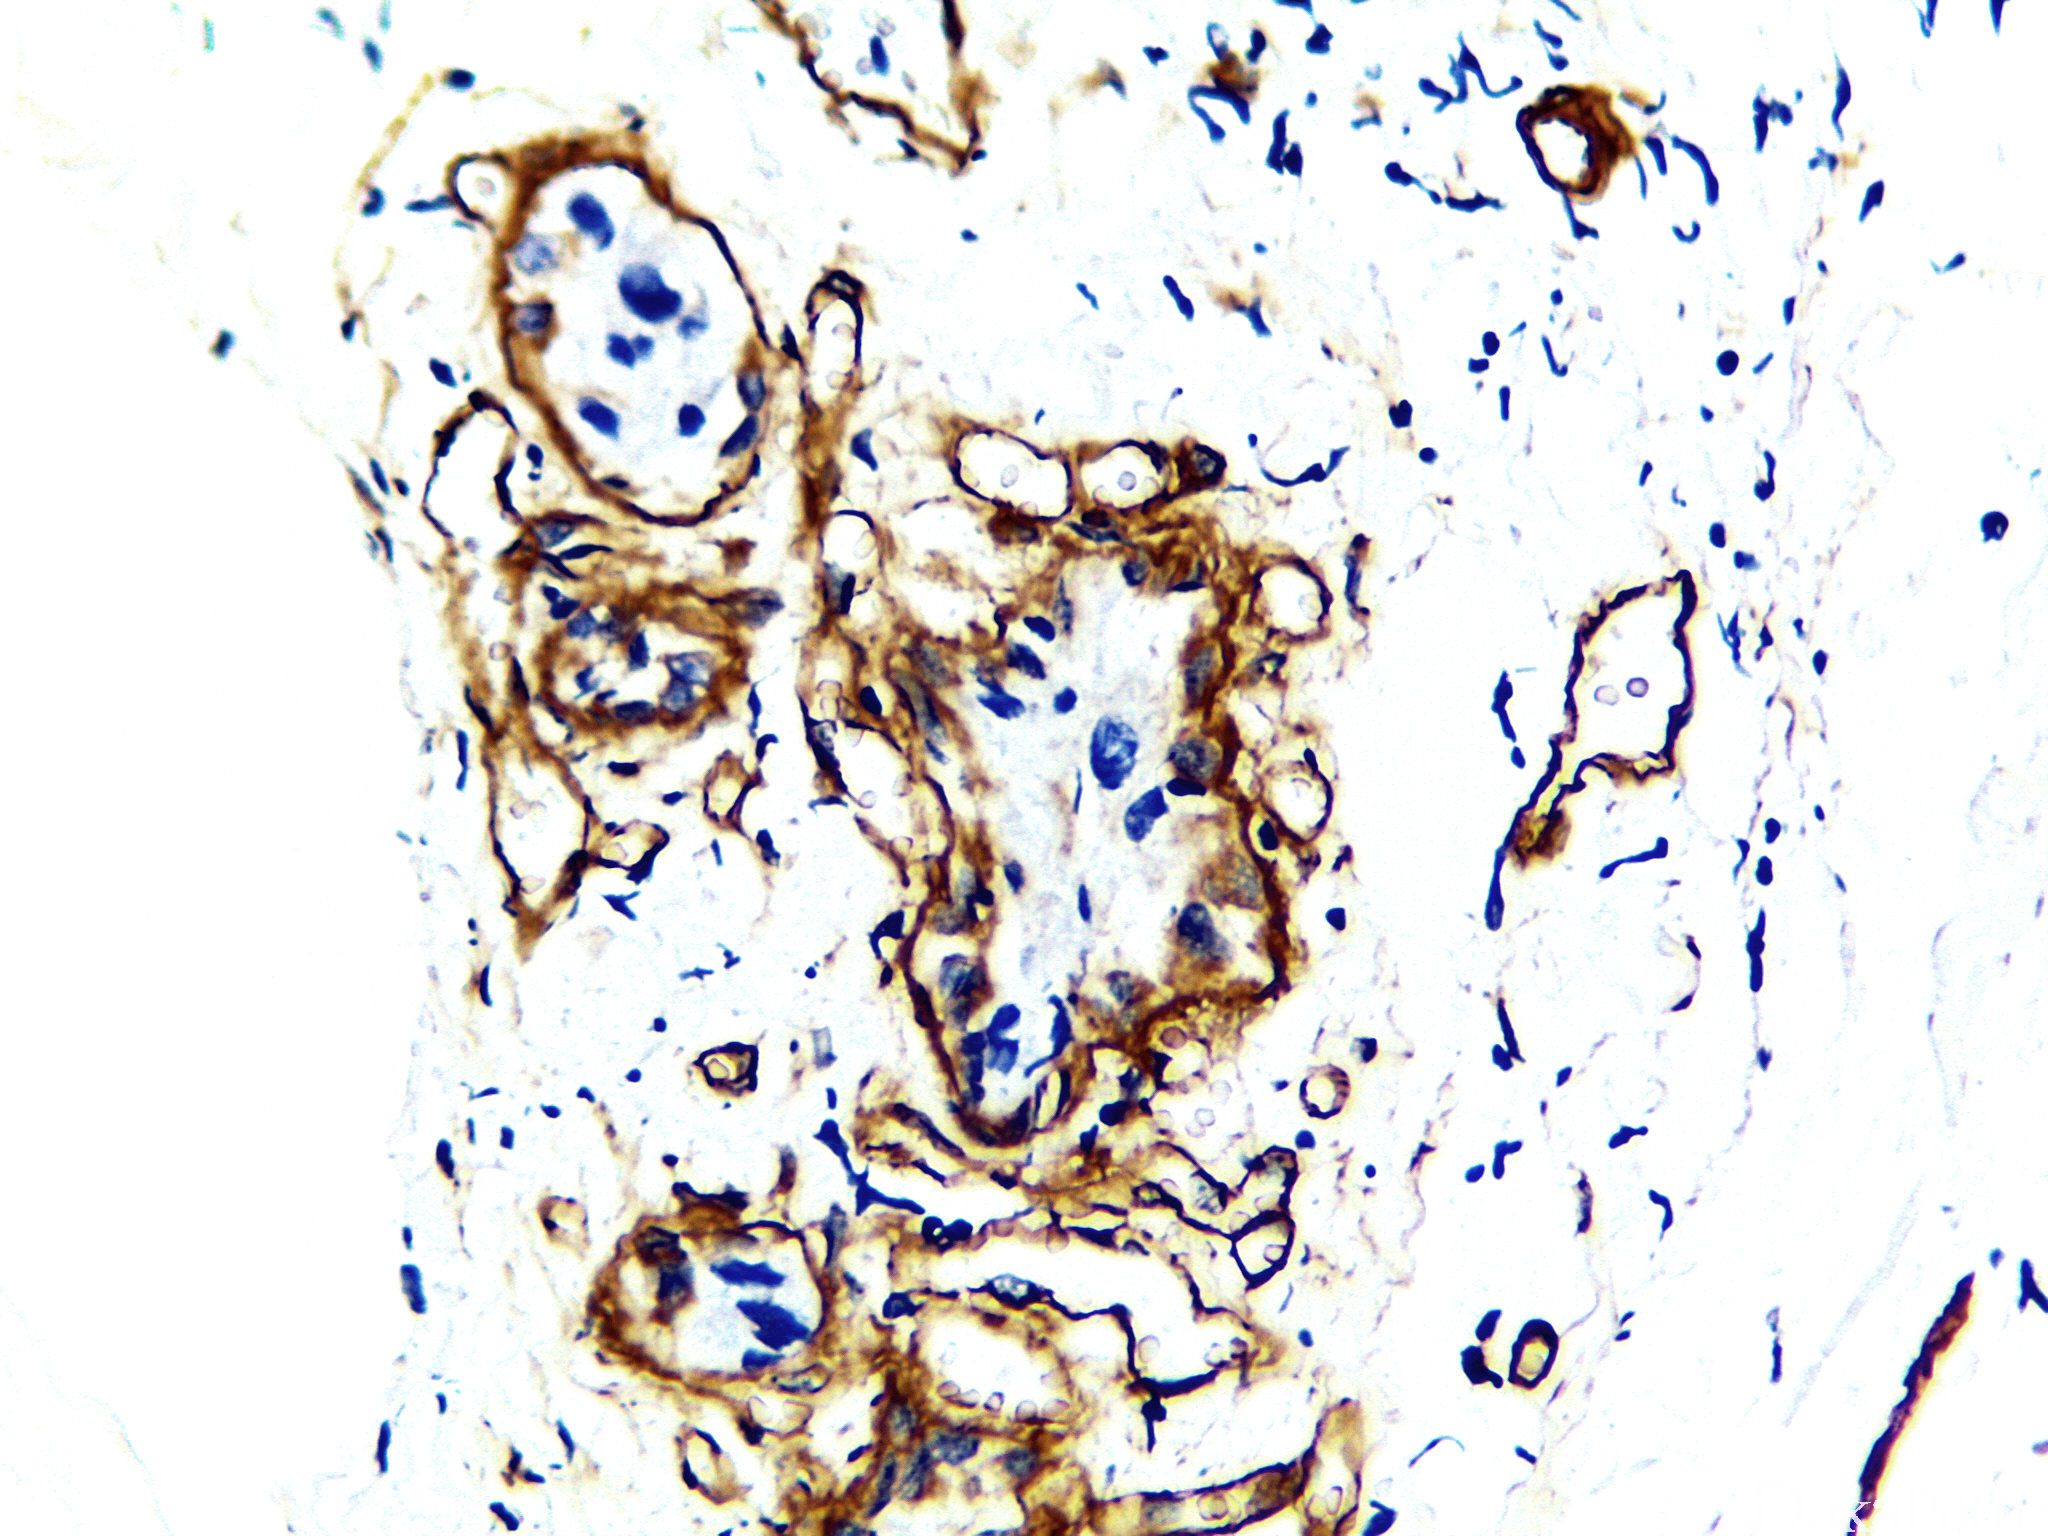

Laminin

基底膜的主要成分之一,链接 IV 型胶原和周围基质,如在上皮、血管周围、神经与大脑软膜鞘内。表达于乳腺的肌上皮细胞。

信号定位: 胞质

肿瘤浸润的鉴别。